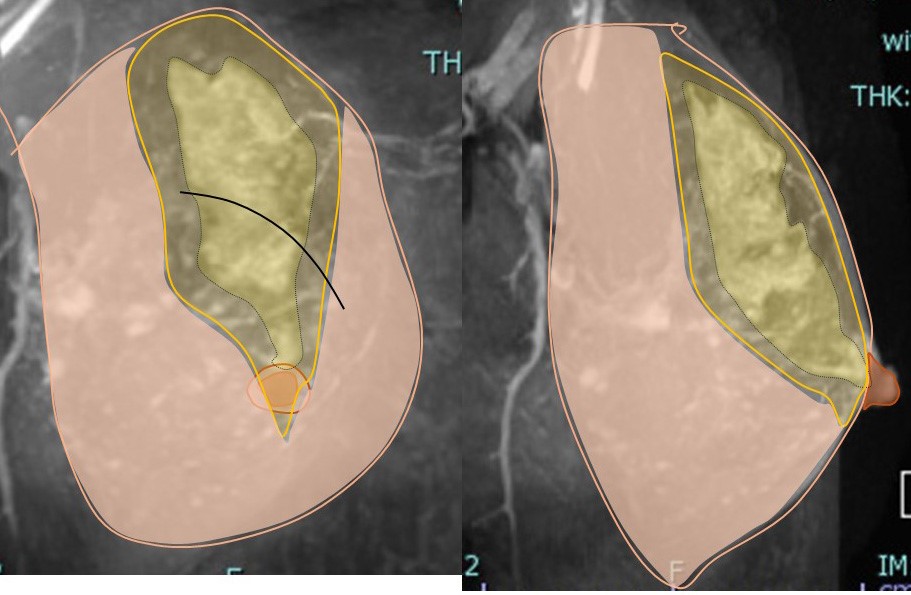

3. 病変に対する(マージンをつけた)切除範囲

乳頭を超えた切除としていますが、乳頭は皮膚を含めて切除しません。

♯側面で見るとよくわかります。

5. 癌の(マージンをつけての)摘出